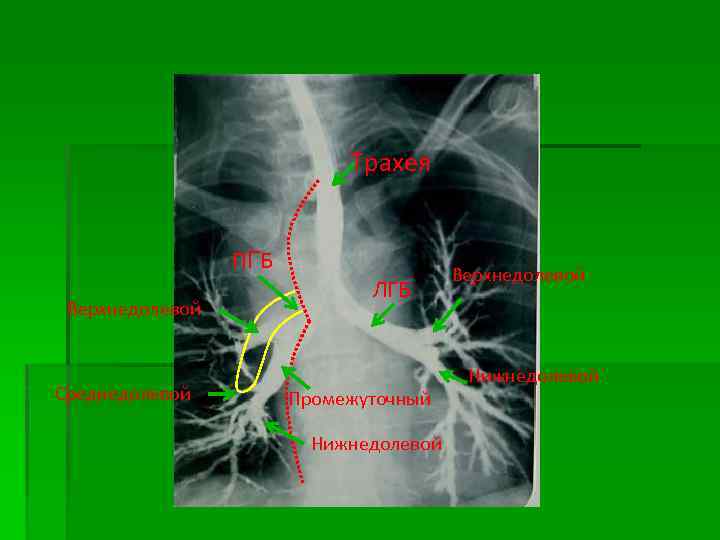

Рентгенанатомия МКК 1. § § Корни легких (критерии структурности): Ширина ЛА (на уровне бифуркации нисходящей и в/долевой справа 15 -17 мм, слева 20 мм) Просвет промежуточного и нижнедолевого бронха – 10 мм Сужение к периферии Резкость (четкость) наружных контуров (деление на головку, тело, хвост) 2. Легочный рисунок (критерии структурности): § Радиарное расхождение § Дихотомическое деление § Уменьшения диаметра к периферии § Четкость наружных контуров § Количество и диаметр сосудов в верхних легочных полях меньше, чем в нижних (1: 2, 1: 3) - обусловлено анатомической строением легких - законы гравитации

Рентгенанатомия МКК Корни легких § § Ширина ЛА (на уровне бифуркации нисходящей и в/долевой) Просвет промежуточного и нижнедолевого бронха – 10 мм Сужение к периферии Резкость (четкость) наружных контуров

Трахея ПГБ Верхнедолевой Среднедолевой ЛГБ Промежуточный Нижнедолевой Верхнедолевой Нижнедолевой